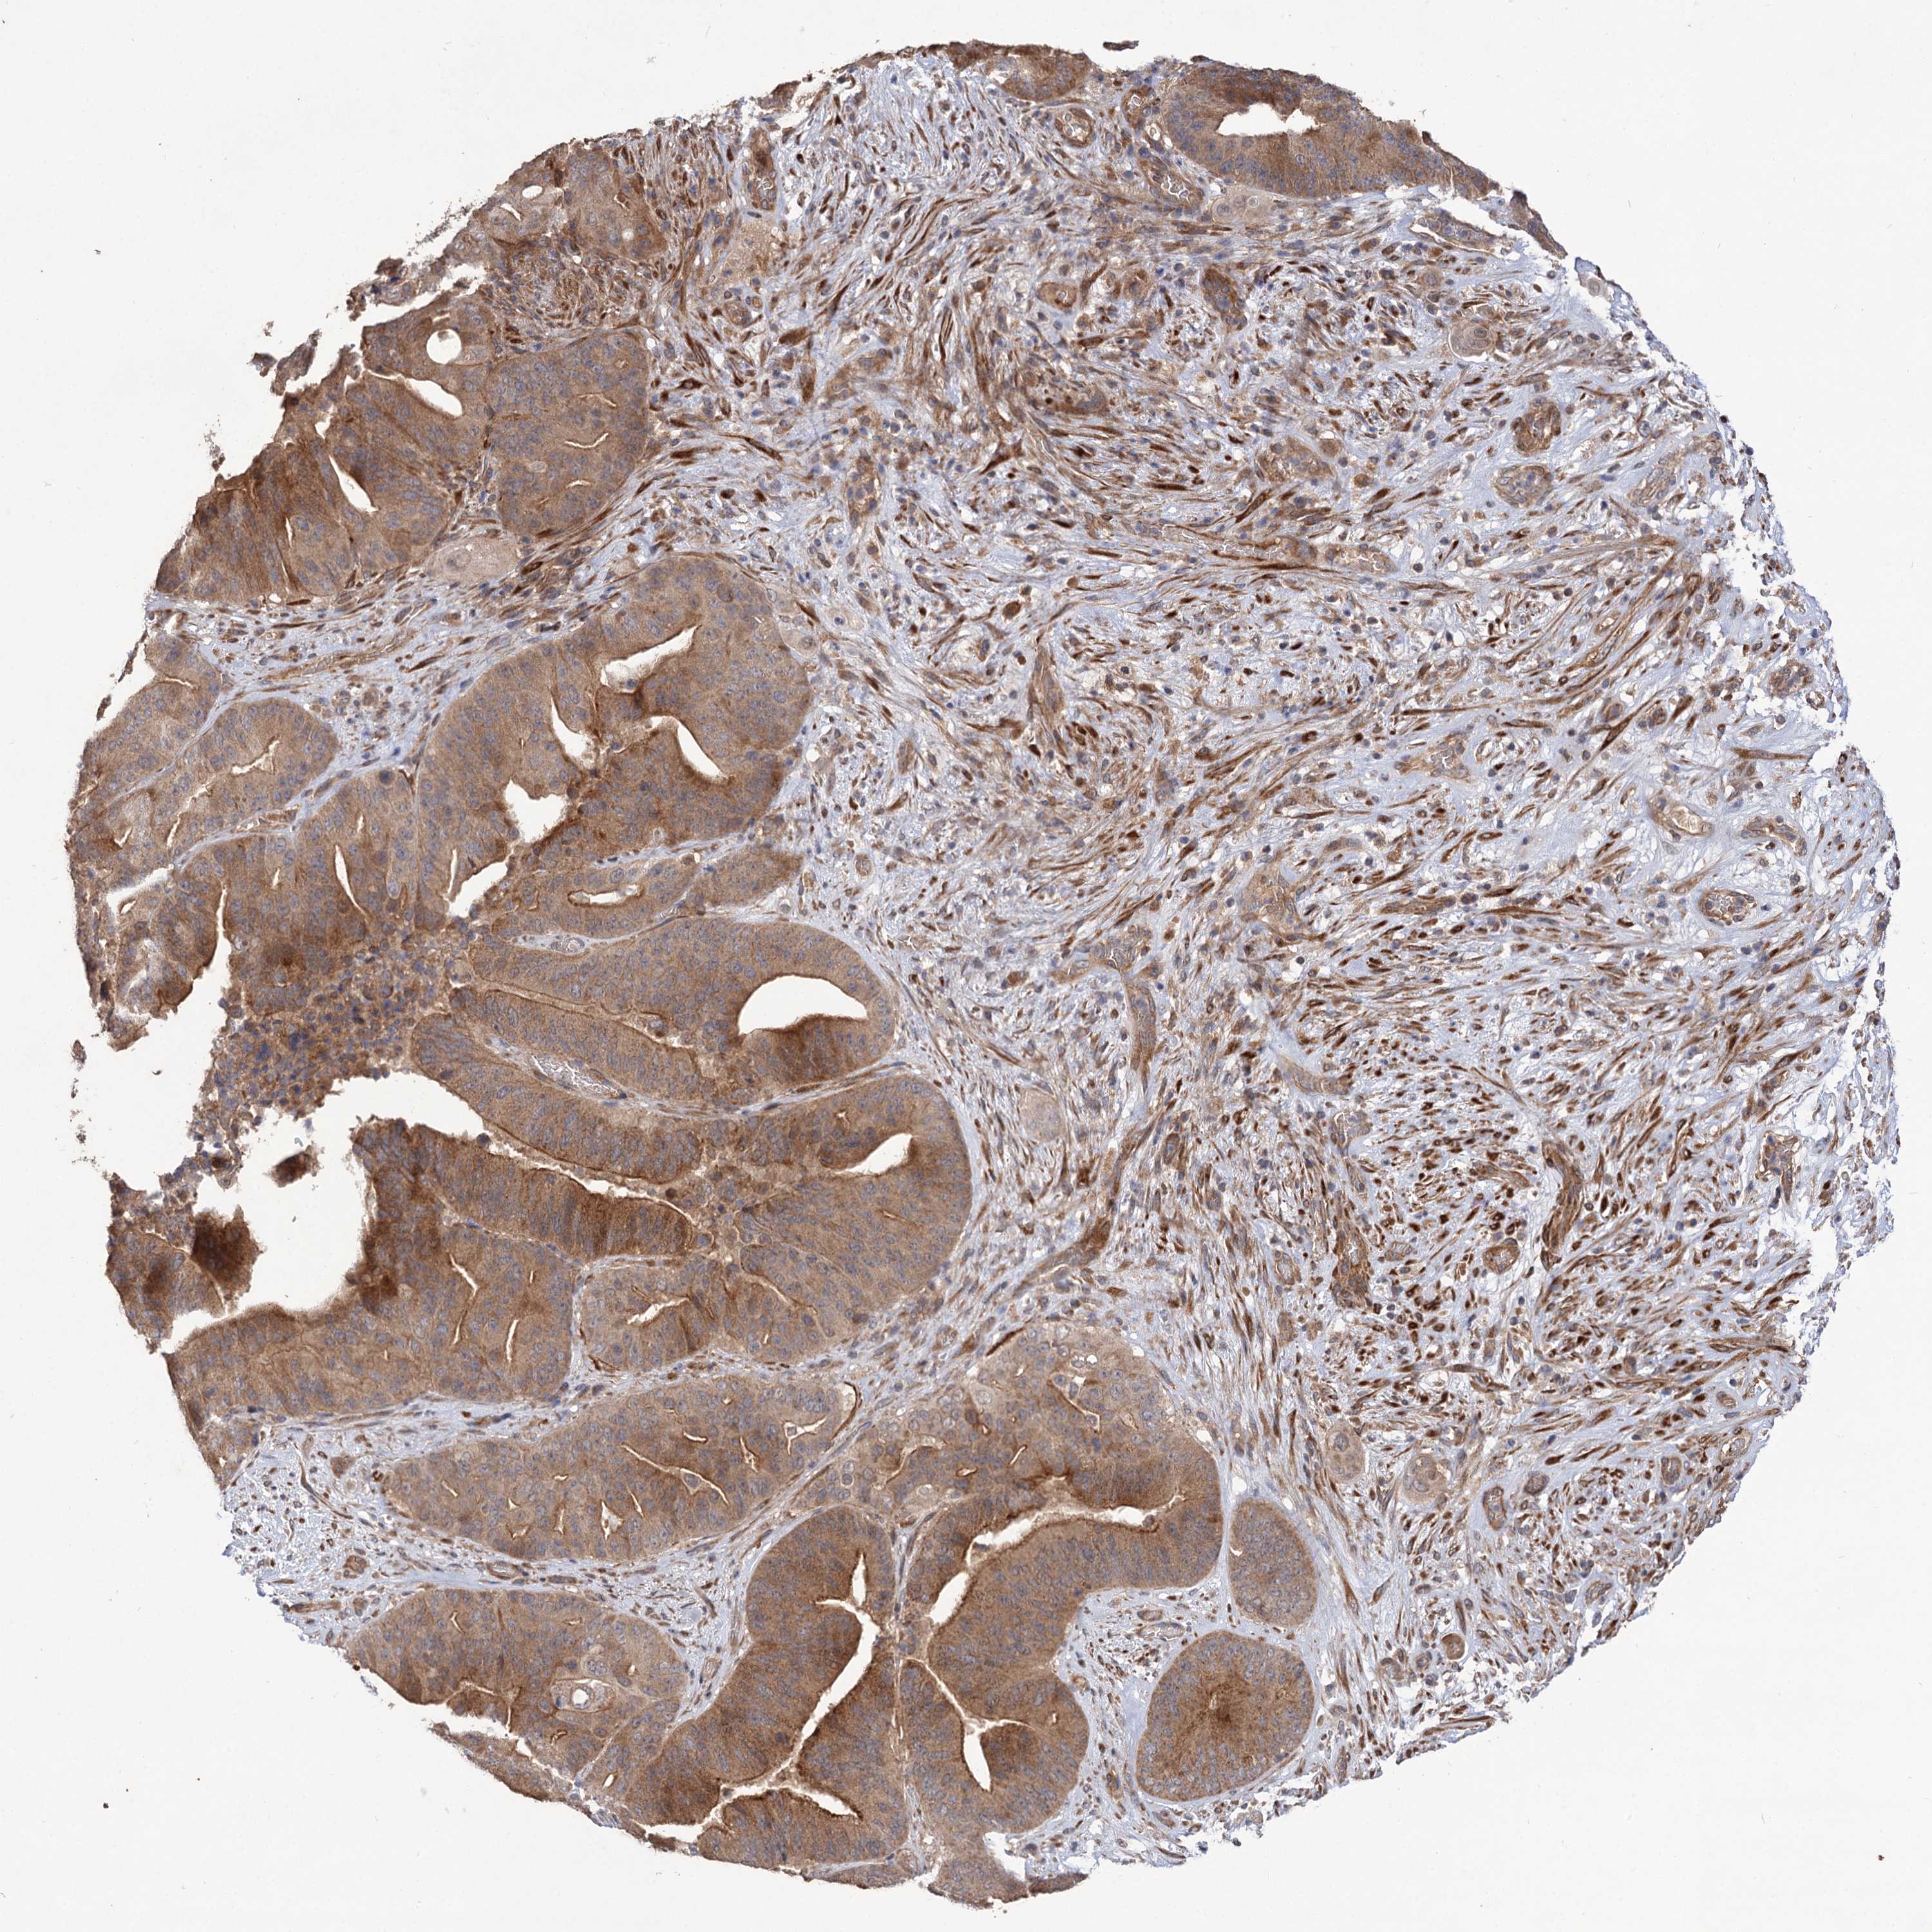

PANCREATIC CANCER - Protein expressioni

A mouse-over function shows sample information and annotation data. Click on an image to view it in a full screen mode. Samples can be filtered based on level of antibody staining by selecting one or several of the following categories: high, medium, low and not detected. The assay and annotation is described here.

Note that samples used for immunohistochemistry by the Human Protein Atlas do not correspond to samples in the TCGA dataset.

Antibody stainingi

Antibody staining in the annotated cell types in the current human tissue is reported as not detected, low, medium, or high, based on conventional immunohistochemistry profiling in selected tissues. This score is based on the combination of the staining intensity and fraction of stained cells.

Each image is clickable and will lead to virtual microscopy that enables deeper exploration of all samples and also displays staining intensity scores, fraction scores and subcellular localization as well as patient and tissue information for each sample.

Antibody HPA038850

Antibody HPA038851

Staining

High

Medium

Low

Not detected

Intensity

Strong

Moderate

Weak

Negative

Quantity

>75%

75%-25%

<25%

None

Location

Nuclear

Cytoplasmic/membranous

Cytoplasmic/membranous,nuclear

Adenocarcinoma, NOS